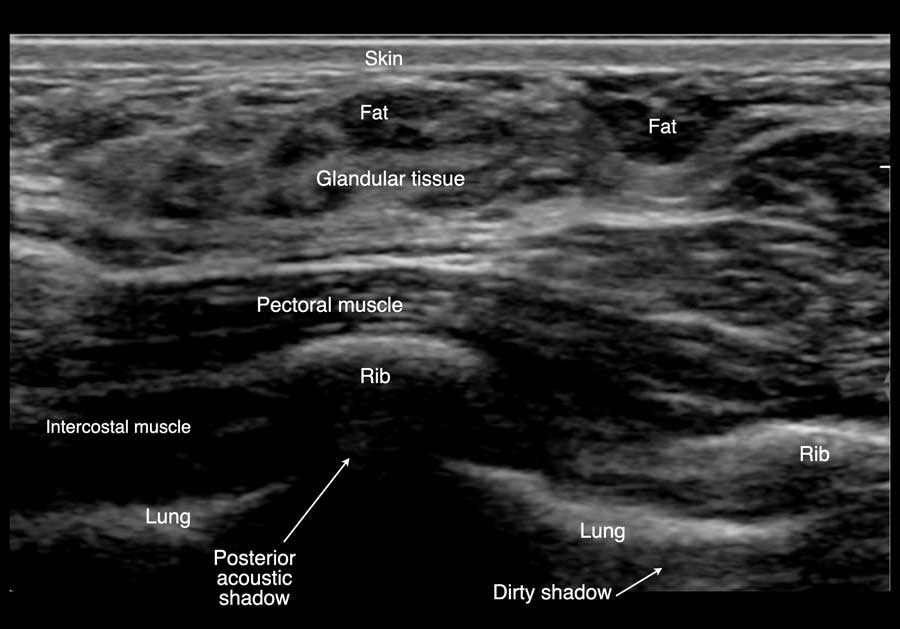

Đây là hình ảnh siêu âm bình thường của tuyến vú.

Lớp xám phía trên là da.

Tiếp theo là sự pha trộn giữa mô mỡ (tối hoặc giảm âm) và mô tuyến (xám sáng hoặc tăng âm).

Lớp có vân sọc phía sau mô vú là cơ ngực.

Phía sau hoặc sâu hơn so với xương sườn có một vùng đen hay bóng cản âm phía sau.

Phổi là lớp có thể quan sát sâu nhất.

Không khí trong phổi phản xạ hầu hết sóng âm, tạo ra một đường sáng hoặc tăng âm với bóng cản bẩn phía sau.

Khi đặt đầu dò lên vú, lớp đầu tiên quan sát được là da, bên dưới là sự pha trộn giữa mô tuyến và mô mỡ.

Lớp sâu nhất là thành ngực với cơ ngực, các xương sườn và các cơ gian sườn.

Phía sau hoặc sâu hơn so với xương sườn, không thể tạo hình ảnh do sóng âm bị hấp thụ, tạo ra một xảo ảnh gọi là bóng cản âm phía sau.

Điều này có nghĩa là không thể quan sát được cấu trúc phía sau xương sườn, và vùng phía sau xương sườn trên hình ảnh sẽ có màu đen.

Phổi bình thường chứa đầy không khí, cũng phản xạ sóng siêu âm.

Bờ trước của phổi tạo ra một đường tăng âm (hyperechoic) hay đường trắng di động theo nhịp thở bình thường (xem video bên dưới).

Sự phản xạ âm của các bóng khí trong phổi tạo ra cái mà chúng ta gọi là bóng cản bẩn (dirty shadow) (xem hình tiếp theo).

Hiện tượng này không rõ rệt như ở xương sườn.